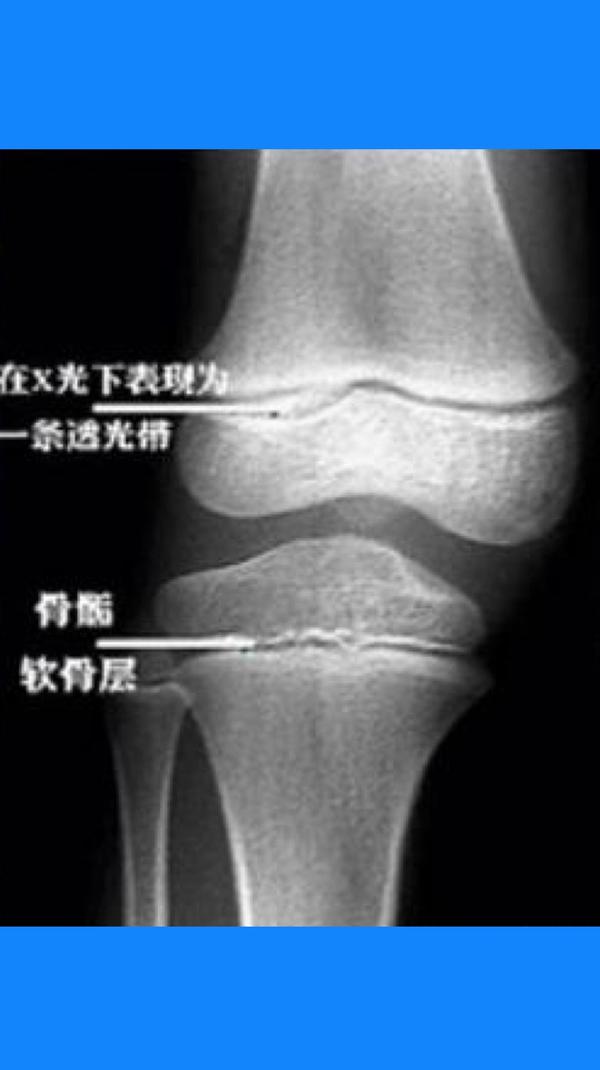

为骨干(diaphysis)或称为骨体(shaft),两端膨大,称为骺(epiphysis)

上图x线中骨与骨之间的一道间隔就是骨骺线未闭合前的形态.

成年后骺软骨骨化,原骺软骨处形成一线状痕迹,称为骺线.